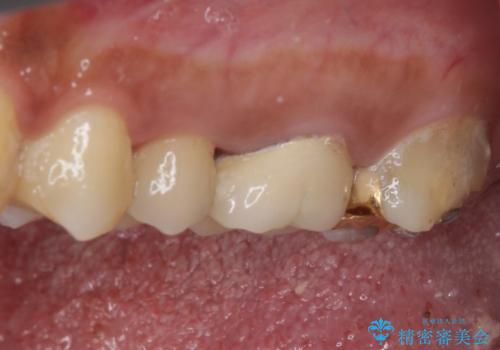

- 食事中にしばしば痛みを感じるとのことで来院された患者様です。

診査をしたところ、レントゲン写真よりとても大きなむし歯があることが分かりました。

虫歯が歯髄腔(神経の部屋)に達している可能性が非常に高かったため、炎症を起こしている神経組織を部分的に切除し、歯根部分の神経組織を保存する治療法が望ましいと考えられました。

処置開始前から神経組織を部分的に除去する可能性が高いことが分かっていたため、ラバーダムなどの環境を整え、無菌的環境下にて処置を進めて行きました。

虫歯は深くまで進行しており、歯冠部の神経から出血が認められました。神経を部分的に除去したところ出血が治まったので、生体親和性の非常に高いセメントにて充填し、仮封をしました。

後日状態を確認したところ、残された神経に異常がなかったため、セラミッククラウンにて補綴治療を行いました。